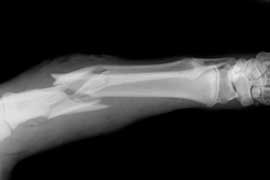

Repensar la evaluación y aprobación de fármacos para la prevención de fracturas

Front. Pharmacol., 15 de mayo de 2017 Se necesitan con urgencia ensayos bien diseñados y largos durante períodos de seguimiento prolongados, midiendo los resultados clínicamente relevantes como la cadera y otras fracturas incapacitantes, con el fin de comprender adecuadamente la relación beneficio-daño de los fármacos comúnmente prescritos.